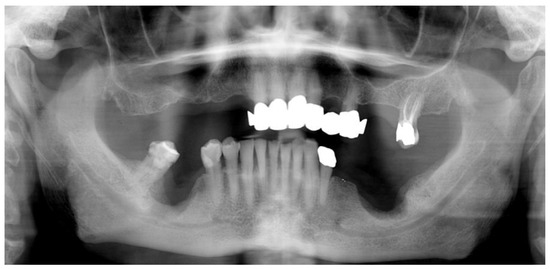

2.1. Case Presentation

- Pre-operative evaluation. The patient undergoes a cone-beam CT exam with a reference plate containing the fiducial markers, fixed on his inferior teeth. The Digital Imaging and Communications in Medicine (DICOM) were imported into the navigation software.